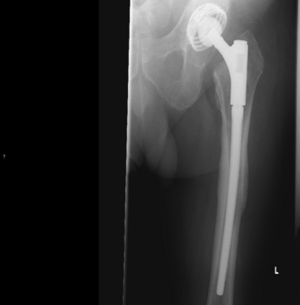

Wechseloperationen sind in der Regel schwieriger, komplexer und komplikationsträchtiger als der Routineeingriff einer Erstimplantation und sollten deshalb vor Eintreten knöcherner Defektsituationen durchgeführt werden. Der richtige Zeitpunkt der Operation ist der Schlüssel zum Erfolg.

Röntgenbild einer Hüftendoprothese im linken Hüftbereich, deutlich sichtbar.

Modulare Langschaftprothese nach Wechseloperation Hüfte